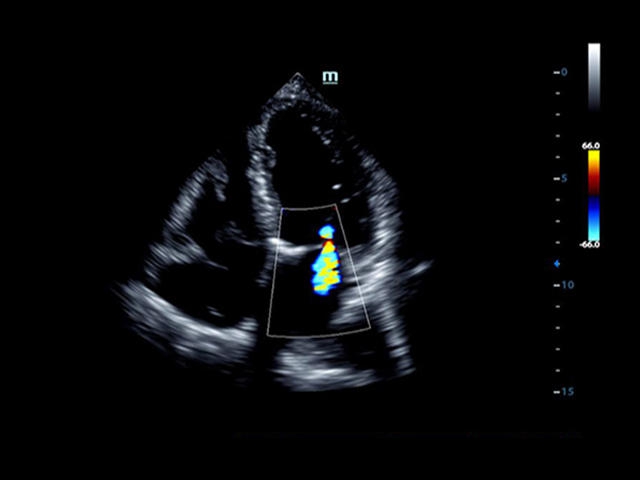

Mindray DC-8 Exp – это ультразвуковой аппарат с архитектурой mQuadro и функцией эластографии Natural Touch. Он оснащен высококлассным 21-дюймовым TFT-монитором с разрешением Full HD. Данный аппарат представляет интерес для специалистов, занимающихся обследованием мягких тканей с использованием эластографии. Режим объемного 4D-сканирования позволяет получать максимально точные диагнозы, сокращая количество неэффективных процедур.

• LVO - опция проведения исследования левого желудочка сердца с применением контрастных веществ;

• TDI (Tissue Doppler imaging, including TDI Color, Power, PW and M mode) - пакет тканевой допплерографии, включая цветное картирование, импульсный тканевой допплер, энергетический тканевой допплер и тканевой М-режим

• LVO - опция проведения исследования левого желудочка с применением контрастных веществ